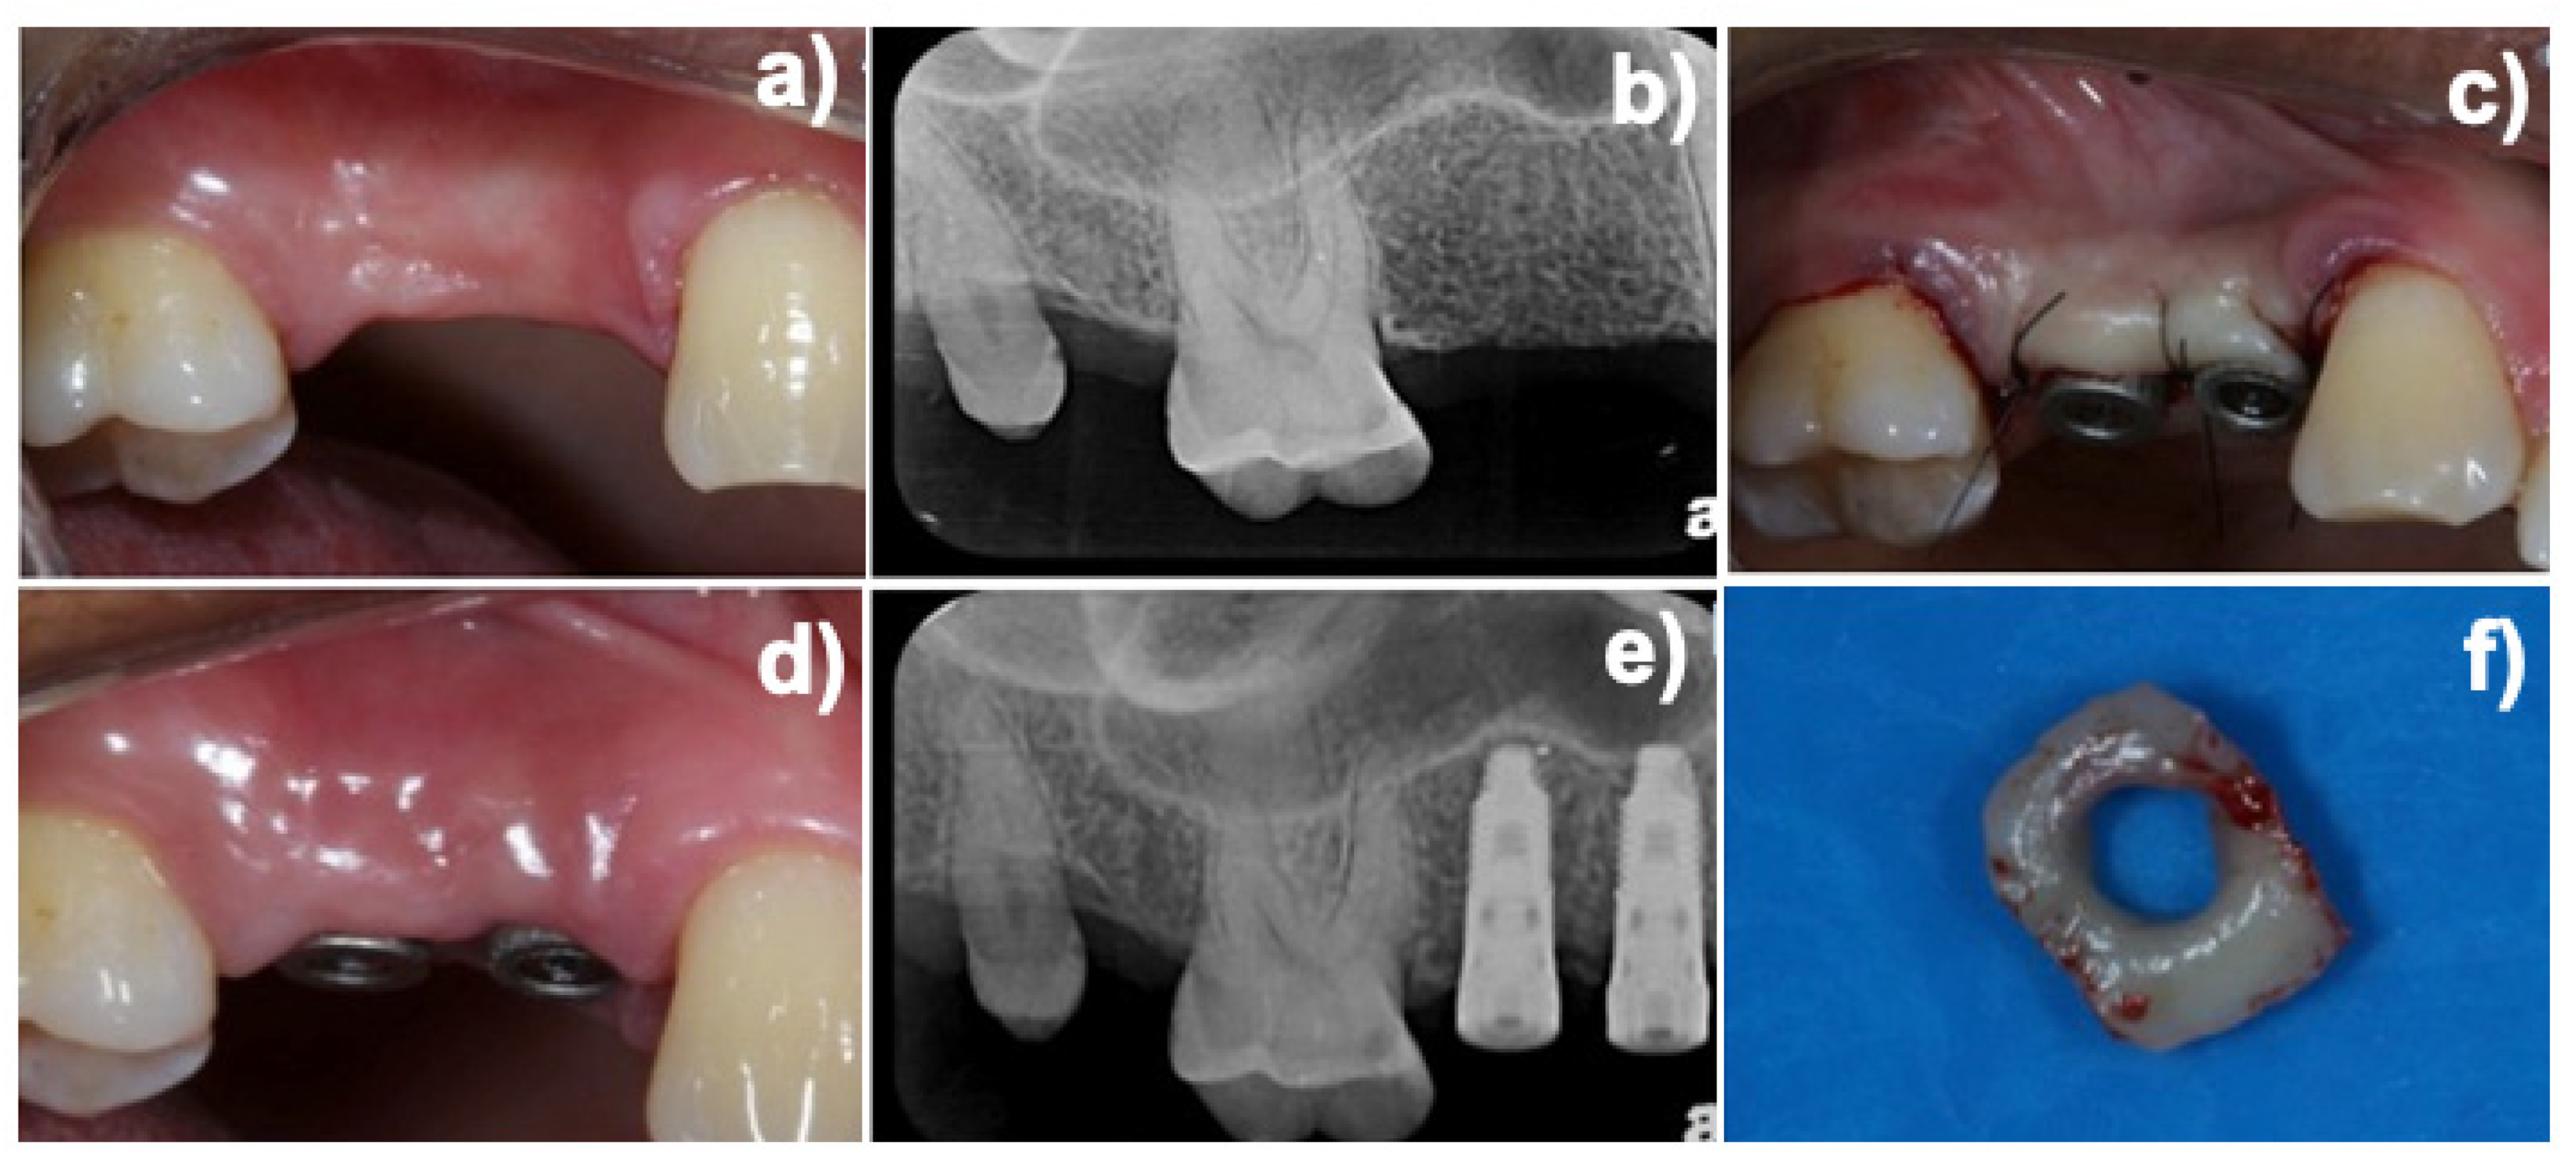

2.2. Experimental Design and Additive Manufactured (DMLS) Healing Abutment

2.4. Gene Expression Evaluation